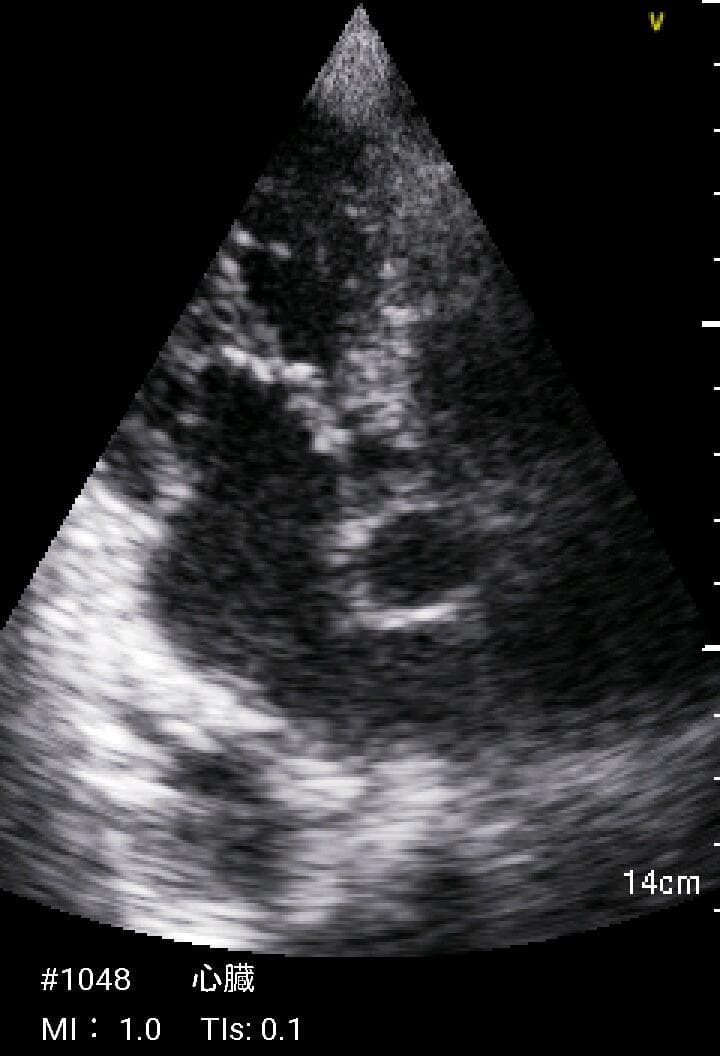

おわかりになる方のみの購入をお願いいたします実際に実施した写真をあげました正常肝臓、胆石症、頸動脈プラーク、同じく頸動脈プラーク、Mrの収縮期、同じくM弁の開放期とA弁の開放期、腹部大動脈瘤、正常の頸動脈、甲状腺右葉の結節、前立腺肥大画像の描出は条件によりますがご検討をお願いいたします経年変化、使用に伴うスレや傷などがあります機能に問題はありませんスキャンは心血管、腹部、体表に対応します外部接続端子のカバーが一部壊れていますが蓋は閉まりますバッテリーはフル充電されますが劣化はあると思います医療用モニタリング機器 Vscan Extend、GE- モデル名: Vscan Extend- ブランド: GE- 色: ホワイト- 機能: 医療用モニタリング機器ご覧いただきありがとうございます。鈴木 ALCARE Youcare-TDc 医療用テープ 25mm 6個。